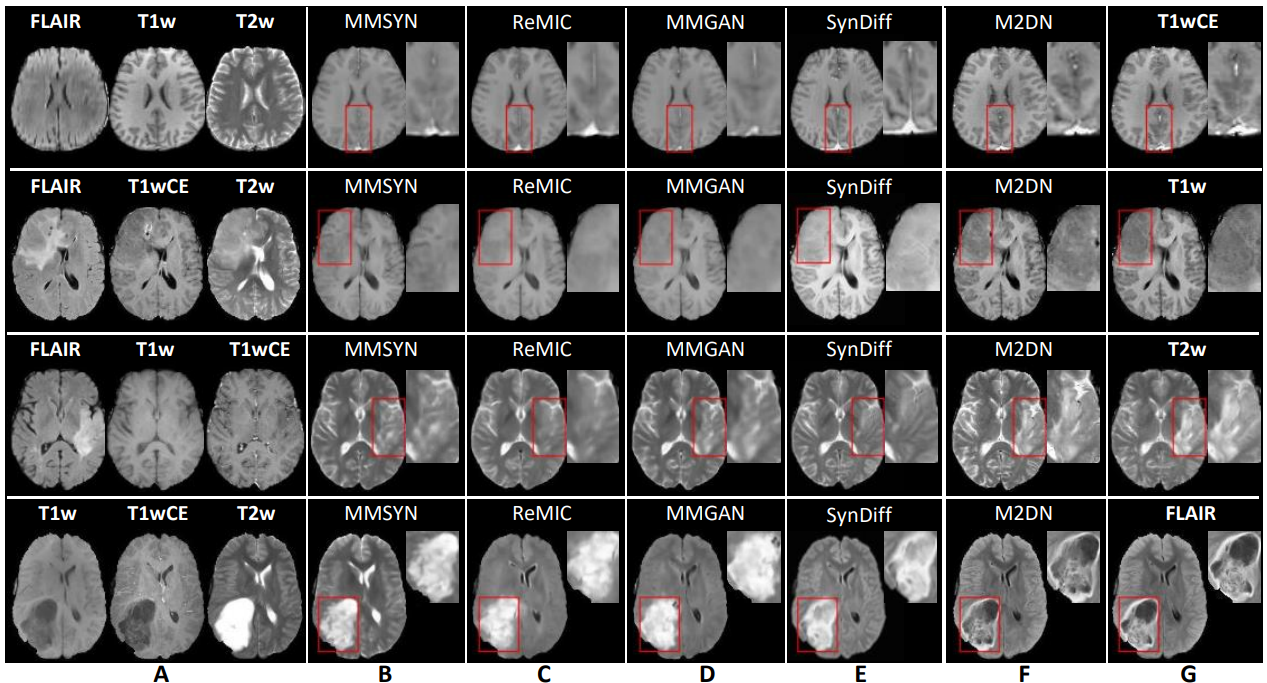

图2. 提出模型与现有方法在BraTS数据集上任意缺失模态合成效果对比。A表示输入模态图,B-F分别展示不同模型的合成结果图,G展示所提出模型的合成结果图。